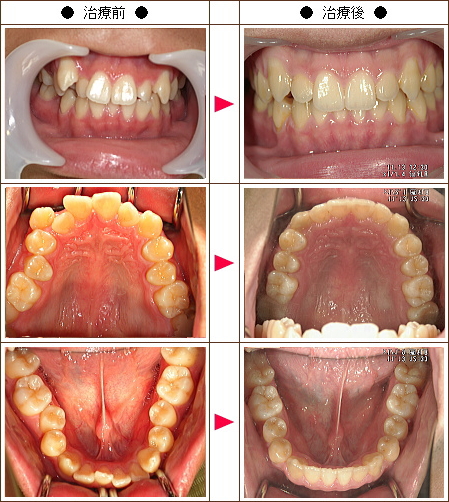

歯のデコボコ矯正症例[I.K.様 35歳 女性]

| 主訴 | 上下の前歯と奥歯のデコボコ |

| 治療方法 | ワイヤー8か月 マウスピース6か月 |

| 治療期間 | 14カ月 |

| 費用(税込み) | 132万円 |

| 治療等の主なリスク、副作用 | 奥歯を親知らずの方向に動かすために親知らずの抜歯は必須になります |

| 治療詳細 | ワイヤー矯正で奥歯を外側に広げて、親知らずの方向に移動して、できたスペースを利用して倒れている奥歯を引っ張り出します。マウスピースで細かい部分を動かしていきます。 |